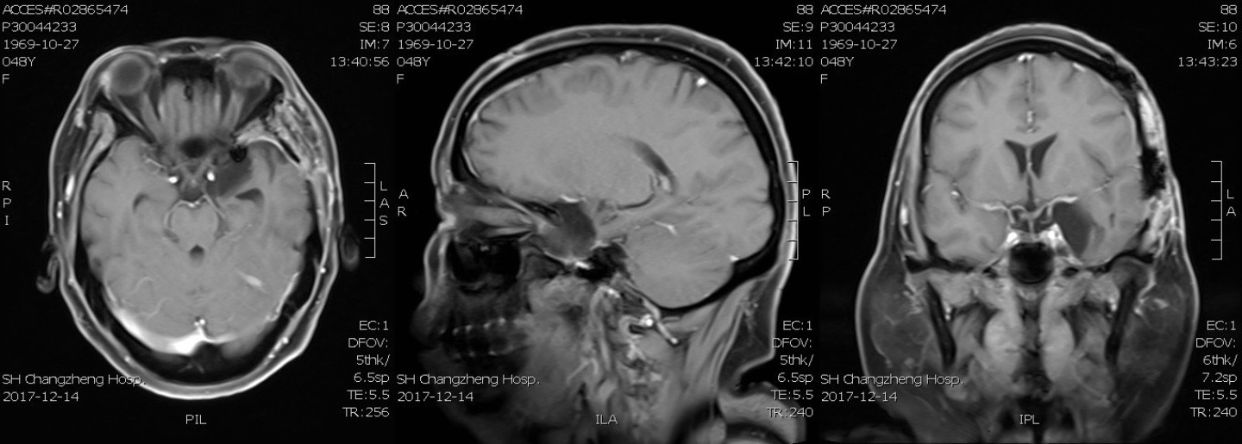

病例1:中年女性,48岁,因发作性头晕、左眼视物模糊半年入院

查体:神志清,对答可,双瞳等大同圆,对光反射正常,粗测视力 L 0.3/R 0.8 ,视野无缺损,无复视,眼球各方向活动正常,四肢肌力正常,深浅感觉正常,病理征(-)。

MRI检查: